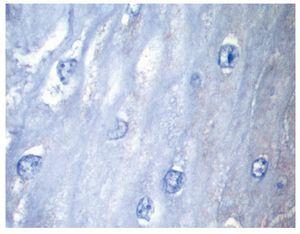

Se presenta el caso de un hombre de 45 años de edad que acudió a consulta por presentar pirosis y regurgitaciones de cinco años de evolución con respuesta parcial al consumo de inhibidores de la bomba de protones (20 mg a 40 mg de omeprazol en terapia a demanda). Por la cronicidad de los síntomas se le realizó una endoscopía del tracto digestivo superior en donde se encontró en el tercio medio del esófago una lesión exofítica de aspecto vegetante, con bordes bien delimitados y de color rosa blanquecino que midió aproximadamente 1 cm de longitud (Figura 1). Ante la sospecha de lesión papilomatosa asociada a virus del papiloma humano (VPH) se realizó biopsia excisional y se envió a estudio anatomopatológico. El resto del estudio endoscópico mostró esofagitis erosiva grado A de Los Angeles. Se prescribió tratamiento con omeprazol 20 mg dos veces al día por seis semanas. Por histología, la lesión presentó epitelio plano estratificado maduro con acantosis y papilomatosis (Figura 2), con centros fibrovasculares (Figura 3) dando un aspecto digitiforme. Las células basales eran grandes pero sin atipias nucleares, en los estratos superficial y medio las células mostraron maduración (Figura 4). Se realizó tinción de inmunohistoquímica para búsqueda de VPH la cual fue negativa (Figura 5). En el seguimiento se realizó endoscopía a los seis meses sin evidencia de recidiva de la lesión.

¿ Figura 3. Acantosis y papilomatosis; mediano aumento.